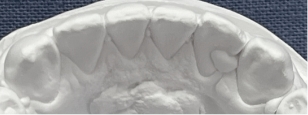

2):当院の矯正の調査法(世界的権威リトル教授の調査方法)

観察方法はPARスコアではなく、もう少しダイレクトな評価になるリトル教授らの方法を使いました。つまり右図のように、後戻りが一番現れやすいと言われている下の前歯において、歯と歯の接触点間の距離をmm単位でデジタル写真上で計測し、それらの合計のミリ数を「指数」とするものです。歯並びが綺麗であれば“0”に近い数字になり、数字が大きいと悪い歯並びを意味します。この写真の歯と歯の接触点間の距離の合計は9.3mmでしたから、指数は9.3になります。